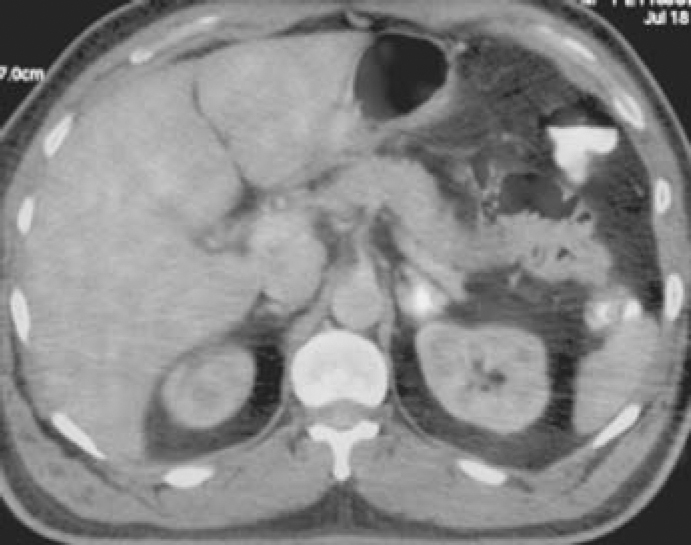

A 50 year old male presented with a 5 × 4 cm ulcero-proliferative growth in left buccal mucosa and a 6 × 5cm mass in left submandibular region of eight months duration. His CT face and neck revealed a 5.8 × 2.4 × 5.6 cm heterogeneously enhancing mass involving the left cheek and adjacent upper and lower lips, 5.8 × 3.8 × 3.7 cm necrotic lymph node in the left submandibular region with peripheral nodular enhancement and multiple left level II – IV lymph nodes, largest measuring 2.4 × 1.9 cm at level II. His whole body 3D PET-CT using 10 mci of FDG was suggestive of increased FDG concentration in mass involving the left cheek and adjacent upper and lower lips (SUV 3.4), 5.8 × 3.8 × 3.7 cm necrotic lymph node in the left submandibular region (SUV 2.5), multiple left level II – IV lymph nodes (SUV 1.8) and left adrenal gland (SUV 1.6) as shown in Fig. 1, Fig. 2. Histopathological examination of the growth in buccal mucosa revealed squamous cell carcinoma. CT-guided FNAC from left adrenal lesion (Fig. 3) was suggestive of squamous cell metastasis in left adrenal. In view of continuous severe pain in buccal growth and impending fungation of cervical nodal mass, the patient was started on palliative local radiotherapy followed by palliative chemotherapy which he tolerated poorly. He had rapid downhill course and was advised supportive and palliative care in view of poor performance status. He succumbed to advanced disseminated disease within three months of presentation.

Fig. 3.

CT guided FNAC smears from left adrenal lesion showing clusters of malignant squamous cells (high power view of malignant cells in inset).